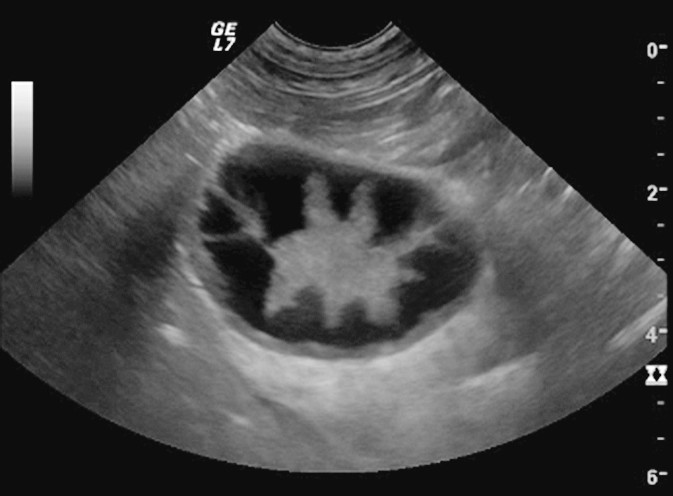

Aus therapeutischer Sicht ist vor allem die Identifikation der Endstadien einer MZ (Stern- und Kiwi-Stadium) aufgrund der Indikation einer Cholezystektomie wichtig. Im Stern-Stadium liegt der echogene Sludge immobil im Zentrum der GB mit sternförmigen Ausläufern zur verdickten GB-Wand hin (Abb. 3). In diesem Stadium ist meist keine deutliche Lamellenstruktur der Wand vorhanden, sondern eine diffus-inhomogene Verdickung.